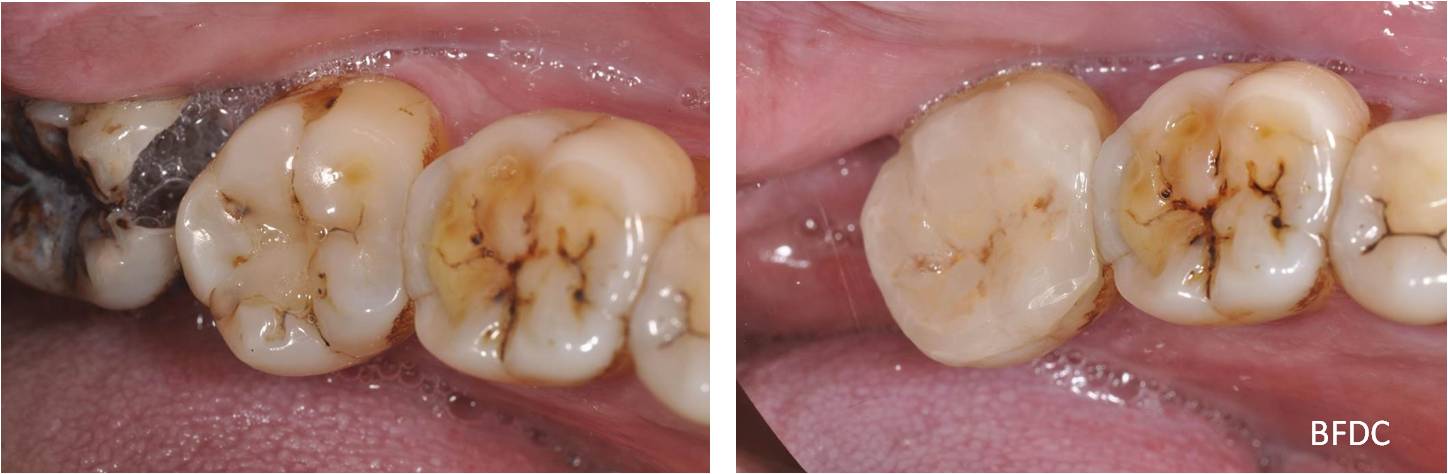

治療後,功能與美觀恢復

術前、術後比較